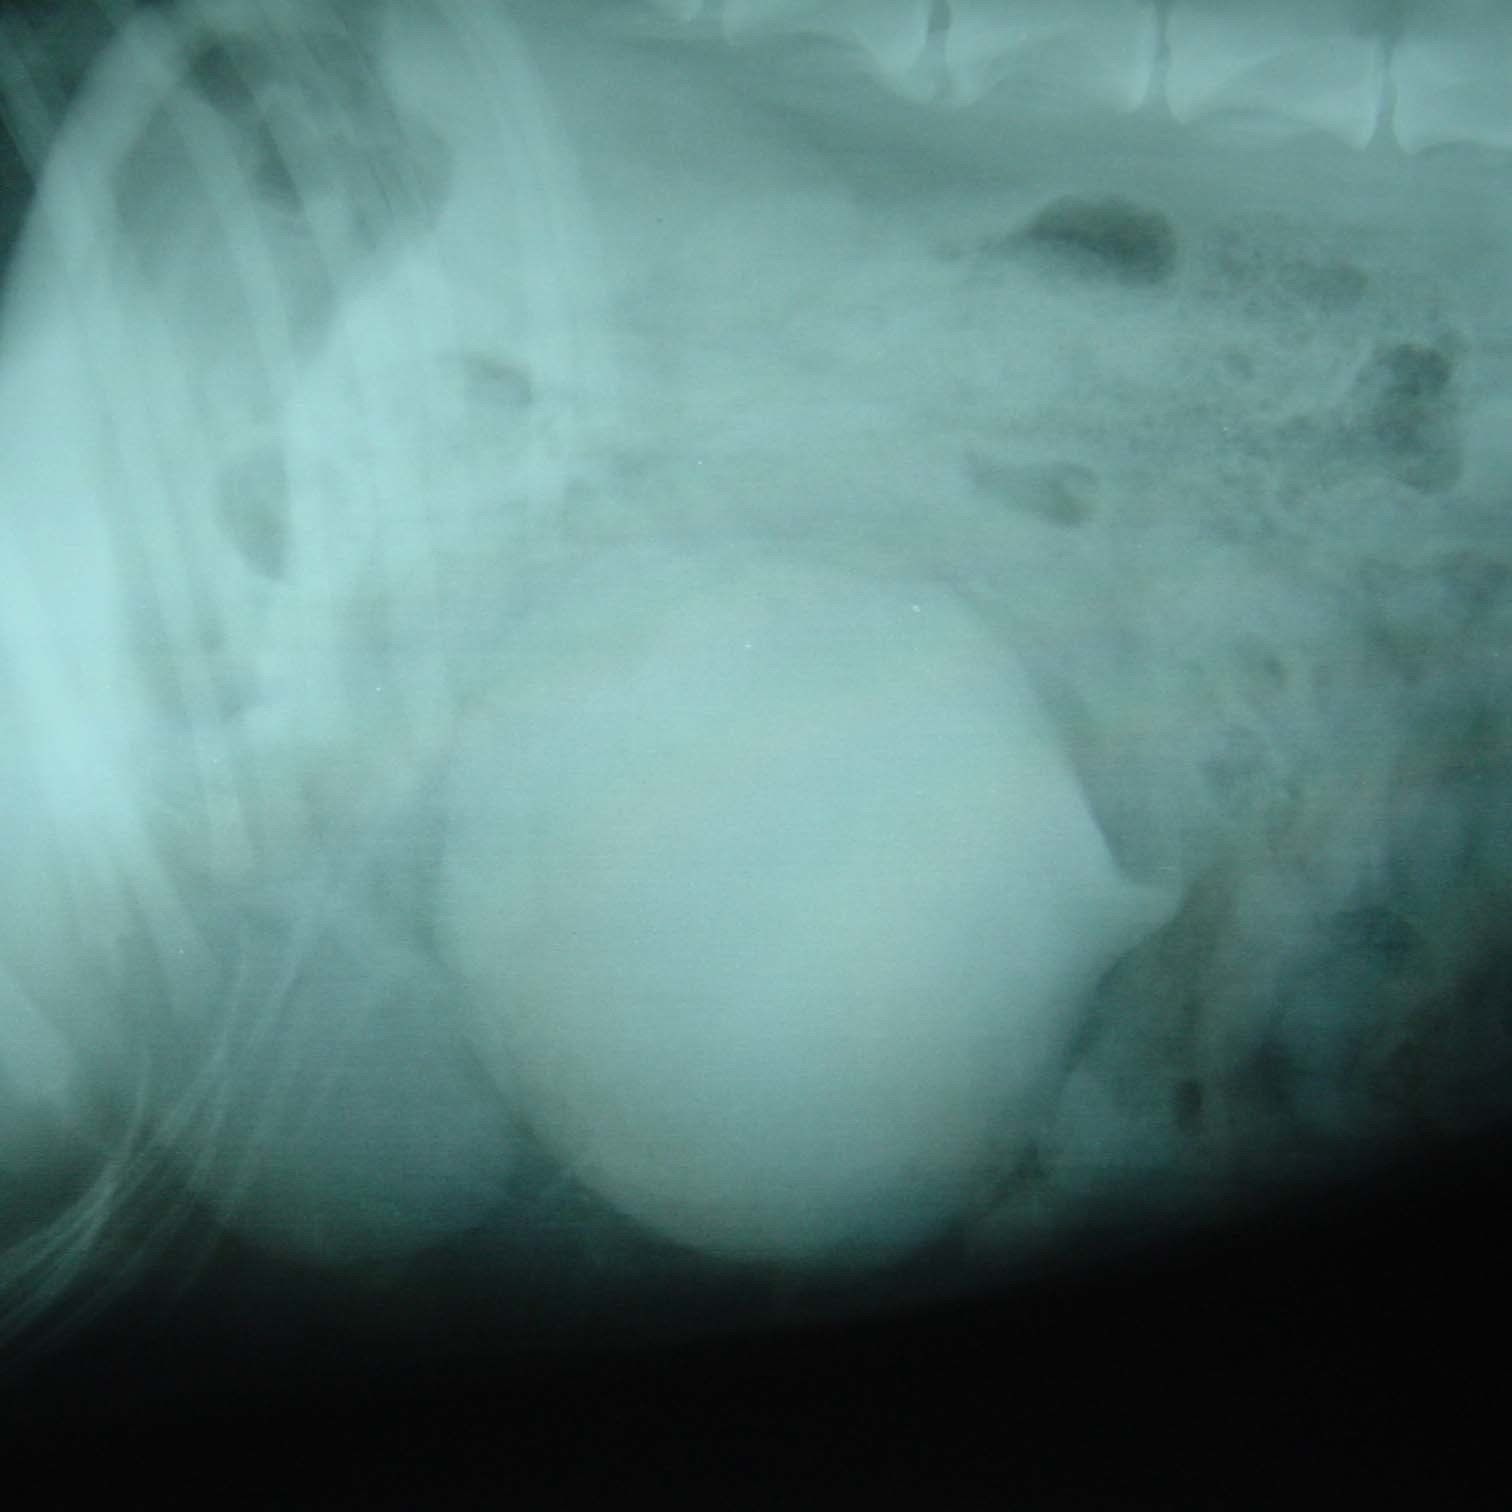

脾臓の腫瘍

脾臓はたくさんの血管が集まっている臓器です。この脾臓に腫瘍ができてしまうと、破裂したときに体内で出血し、貧血やショック症状などを起こす場合があります。免疫力が低下しやすいシニア犬期によく見られ、初期段階ではわかりやすい症状があらわれないため、飼い主さんでは気づきにくく、エコー検査で見つかるケースが多いです。

脾臓の腫瘍のレントゲン写真。中央の丸く白いところが腫瘍部分です。